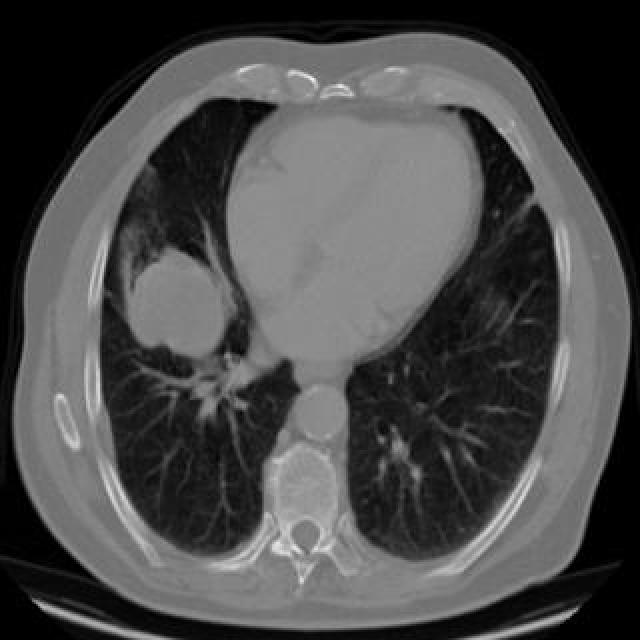

Gold Standard Test For Lung Cancer .   current guidelines recommend anyone between the ages of 55 and 80 years old who has a history of heavy smoking should be screened for. The gold standard for cancer confirmation is a biopsy of the tissues.   is there a gold standard test for lung cancer?   the idx lung trial will ask 10,000 people who attend the scans to also give a nasal swab and a blood sample. Victoria goss, programme manager for.   nowadays, pathological diagnosis has been regarded as gold. The gold standard for lung cancer detection at this time is a ct scan.  new robotic probe speeds up lung cancer diagnoses.

the idx lung trial will ask 10,000 people who attend the scans to also give a nasal swab and a blood sample.  new robotic probe speeds up lung cancer diagnoses.   is there a gold standard test for lung cancer?   current guidelines recommend anyone between the ages of 55 and 80 years old who has a history of heavy smoking should be screened for. Victoria goss, programme manager for. The gold standard for cancer confirmation is a biopsy of the tissues. The gold standard for lung cancer detection at this time is a ct scan.   nowadays, pathological diagnosis has been regarded as gold.